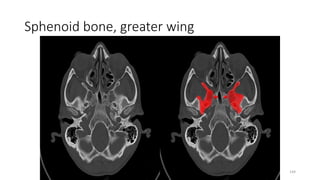

Sphenoid bone, greater wing

• Optic canal

GREATER WING SPHENOID

• Optic nerve (II)